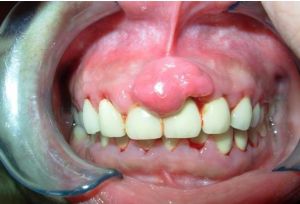

妊娠型牙齦瘤牙齦瘤以女性患者多見,中青年發病較多。多發生於唇頰側齦乳頭,以雙尖牙區最常見,舌、齶處少見,一般為單個牙發生。腫塊較局限,大小不一,通常呈圓形、橢圓形,有時為分頁狀,有的有蒂如息肉狀,有的無蒂基底寬廣。血管型和肉芽腫型者質地柔軟、色紅;纖維型者質地較韌且硬,顏色粉紅。腫塊一般生長緩慢,但在女性妊娠期可迅速增大。腫塊長大可以遮蓋部分牙面及牙槽突,表面可見牙壓痕,易被咬傷而發生潰瘍、出血或伴發感染。一般無痛,腫物表面發生潰瘍時可感覺疼痛。長期存在的較大腫塊可以壓迫並破壞牙槽骨壁X線示局部牙周膜增寬,致使牙鬆動、移位。

(2)妊娠瘤易在婦女懷孕期(第4~9月)發生,分娩結束後可以退縮。